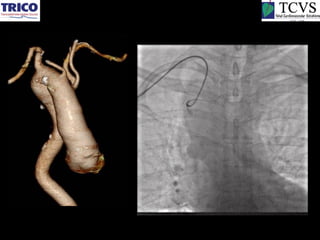

Effect of dilatation and distortion of aorta

Schematic diagram of different loops

produced due to distortion of aorta

•   Normal

•   Z–loop

•   Roller-coaster loop

•   Cobra loop

Arteria Lusoria